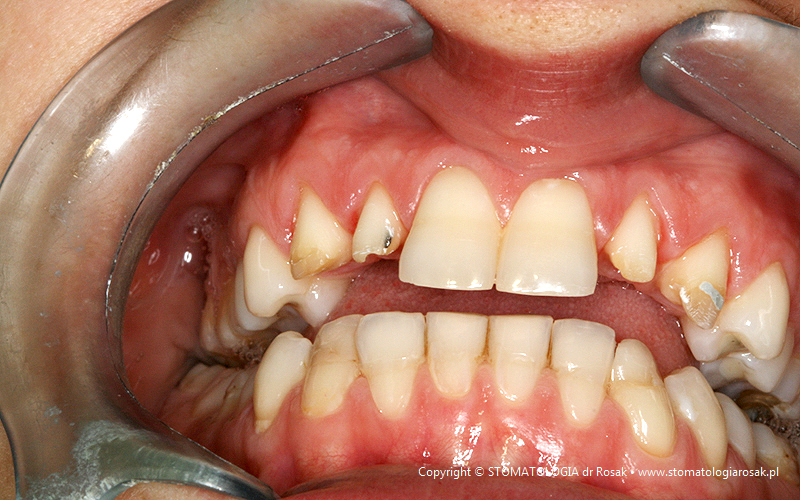

9. Pacjent lat 57- zgłosił się celem usunięcia zniszczonych zębów i wykonania protez ruchomych całkowitych.

NIE USUNĘLIŚMY - ANI JEDNEGO ZĘBA!!!

| 9a. Przed leczeniem |

9b. Gotowe korony i mosty porcelanowe na górze

(trójkę górną prawą pacjent zażyczył sobie nie korygować)

oraz w żuchwie tzw. czapeczki pokrywające oraz zatrzaski kulowe dla lepszego utrzymania protezy ruchomej dolnej |